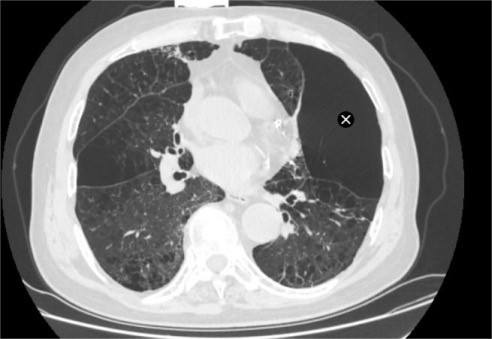

家属带着陈大爷辗转求医,来到苏州大学附属第四医院呼吸内科蒋军红主任门诊就诊。完善胸部CT检查后显示,陈大爷患有异质性肺气肿,肺部病变区域分布极不均衡,部分肺叶过度充气、丧失正常通气功能,形成“无效通气腔”,进一步加重了正常肺组织的负担,这也是他经药物治疗后仍无法缓解症状的核心原因。

该术种的适用范围:确诊为重度/极重度慢性阻塞性肺疾病(GOLD 3-4级),合并异质性肺气肿(肺部病变分布不均,有明确过度充气的靶肺叶);长期规范吸入药物治疗后,仍存在明显胸闷、气喘、呼吸困难症状,活动耐量极差,日常活动受限;胸部CT提示叶间裂完整,病变肺叶与健康肺叶分界清晰,无明显侧支通气。